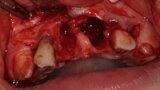

Ryc. 3_Zęby 11 i 21 po ekstrakcji.